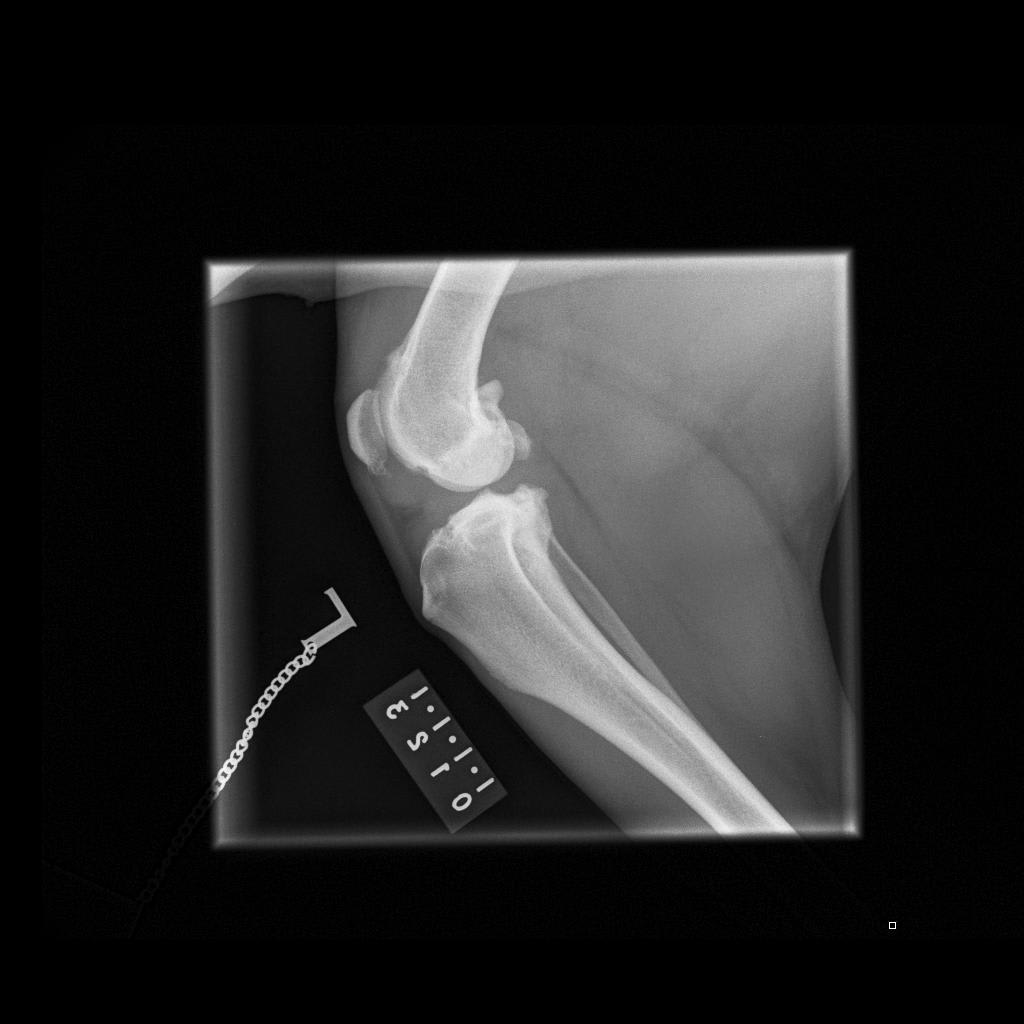

I’m after a 2nd opinion; not sure what to do.My dog is fully insured so not a decision based on cost.She damaged rear left cruciate ligament back in June. Since then her limp vanished only came back recently after intense running. My vet took x-rays (attached). She is a rescue dog,about 6 yrs old.I have also attached pic of her so you get an idea of the type of dog she is. 31kg. What’s best-operate or not? I want to do what’s best for her without undue pain or anxiety. I’m at a loss what to do.

The answer to your question really comes down to her examination and your goals. It is possible for a cruciate ligament to be partially torn or fully torn. If it is fully torn, the knee is unstable and surgery is the best option to stabilize the knee and slow down the development of arthritis in the joint. If the cruciate ligament is only partially torn, you can see signs like you have in Hambro where she seems pretty normal unless she injures the cruciate ligament again with high activity. For a large dog who is young, partial cruciate ligament injures are often problematic because they inhibit dogs from being able to play normally without being painful, but it sounds like Hambro has done well for 6 months. Another consideration is that if she has a partial tear, she may completely tear the cruciate ligament in the future which will necessitate surgery. There is also a potential complication of cruciate injuries that involve a tear in the meniscus. If that happens, she will be consistently lame and will need surgery. Unfortunately, only you can decide on the right answer for Hambro. Surgery provides the best possibility for return to normal activity without lameness, but certainly isn't without potential risks and complications. I have attached a handout on cruciate ligament injuries below. https://www.veterinarypartner.com/Content.plx?P=A&S=0&C=0&A=1975 Finally, if this is a partial cruciate injury and you would like to avoid surgery, I would recommend trying to find a rehabilitation veterinarian to help you with physical therapy exercises to strengthen Hambro. They will also be able to give you a second opinion. Hopefully you can find a vet in the UK at this site. http://www.caninerehabinstitute.com/Find_A_Therapist.html http://www.caninerehabinstitute.com/action.lasso Good luck! I hope that was helpful. Thanks for using PetCoach.